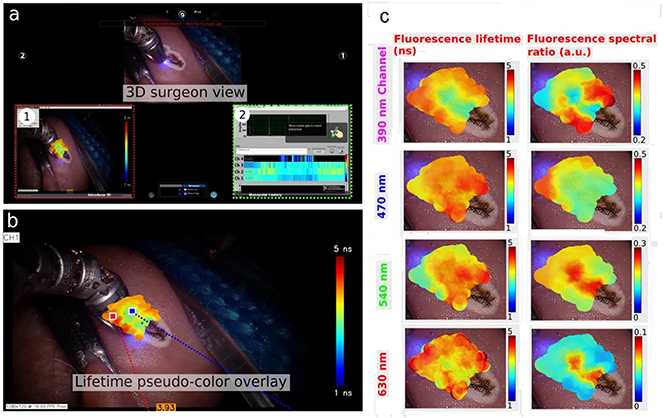

NIMMS (Next Ion Medical Machine Study). https://www.hitriplus.eu/ Heavy Ion Therapy Research Integration plus.